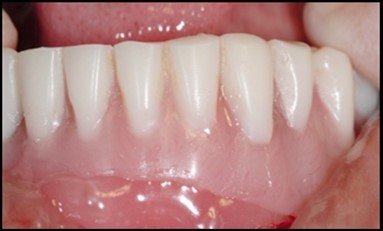

Figure 12.Insertion of the lower denture

Insertion of the lower denture

General criteria for survival and success of implants have been used to evaluate the efficacy of immediately loading mandibular implants. For example, survival criteria include how the implant performs, particularly regarding the absence of pain, infection, and paresthesia. Implant immobility and the absence of periimplant radiolucency under radiography are 2 more criteria of implant survivability.6, 7 Success criteria include the additional element of absence of vertical bone loss; specifically, less than 1 mm during the first year and less than 0.2 mm annually thereafter. Granted that success rates for immediatel oading of implants in the edentulous mandible are not as high as rates for the traditional 2-stage approach, conditions nevertheless often warrant the 1-stage surgical option described here.7, 8, 9 (Figure 12).

Using 2 implants and retentive anchors for the retention of a mandibular complete denture is, in terms of immediate costs, one of the most affordable implant procedures. 8, 9, 14 With ideal placement of the implant, the stability of the prosthesis is excellent and the lingual dimensions of the denture can in some cases be reduced to the level of mylohyoid line, providing more space for the tongue and greater comfort than with conventional complete dentures.8, 9, 10, 15 However, if the labial musculature is tense or the amount of attached gingiva is limited, the implants should not be placed too deep or too labially, which might prevent gingival growth over the abutments. In those cases, ball anchor abutments with elevated shoulders can be used to improve implant anatomy.8, 9, 10 (Figure 12).